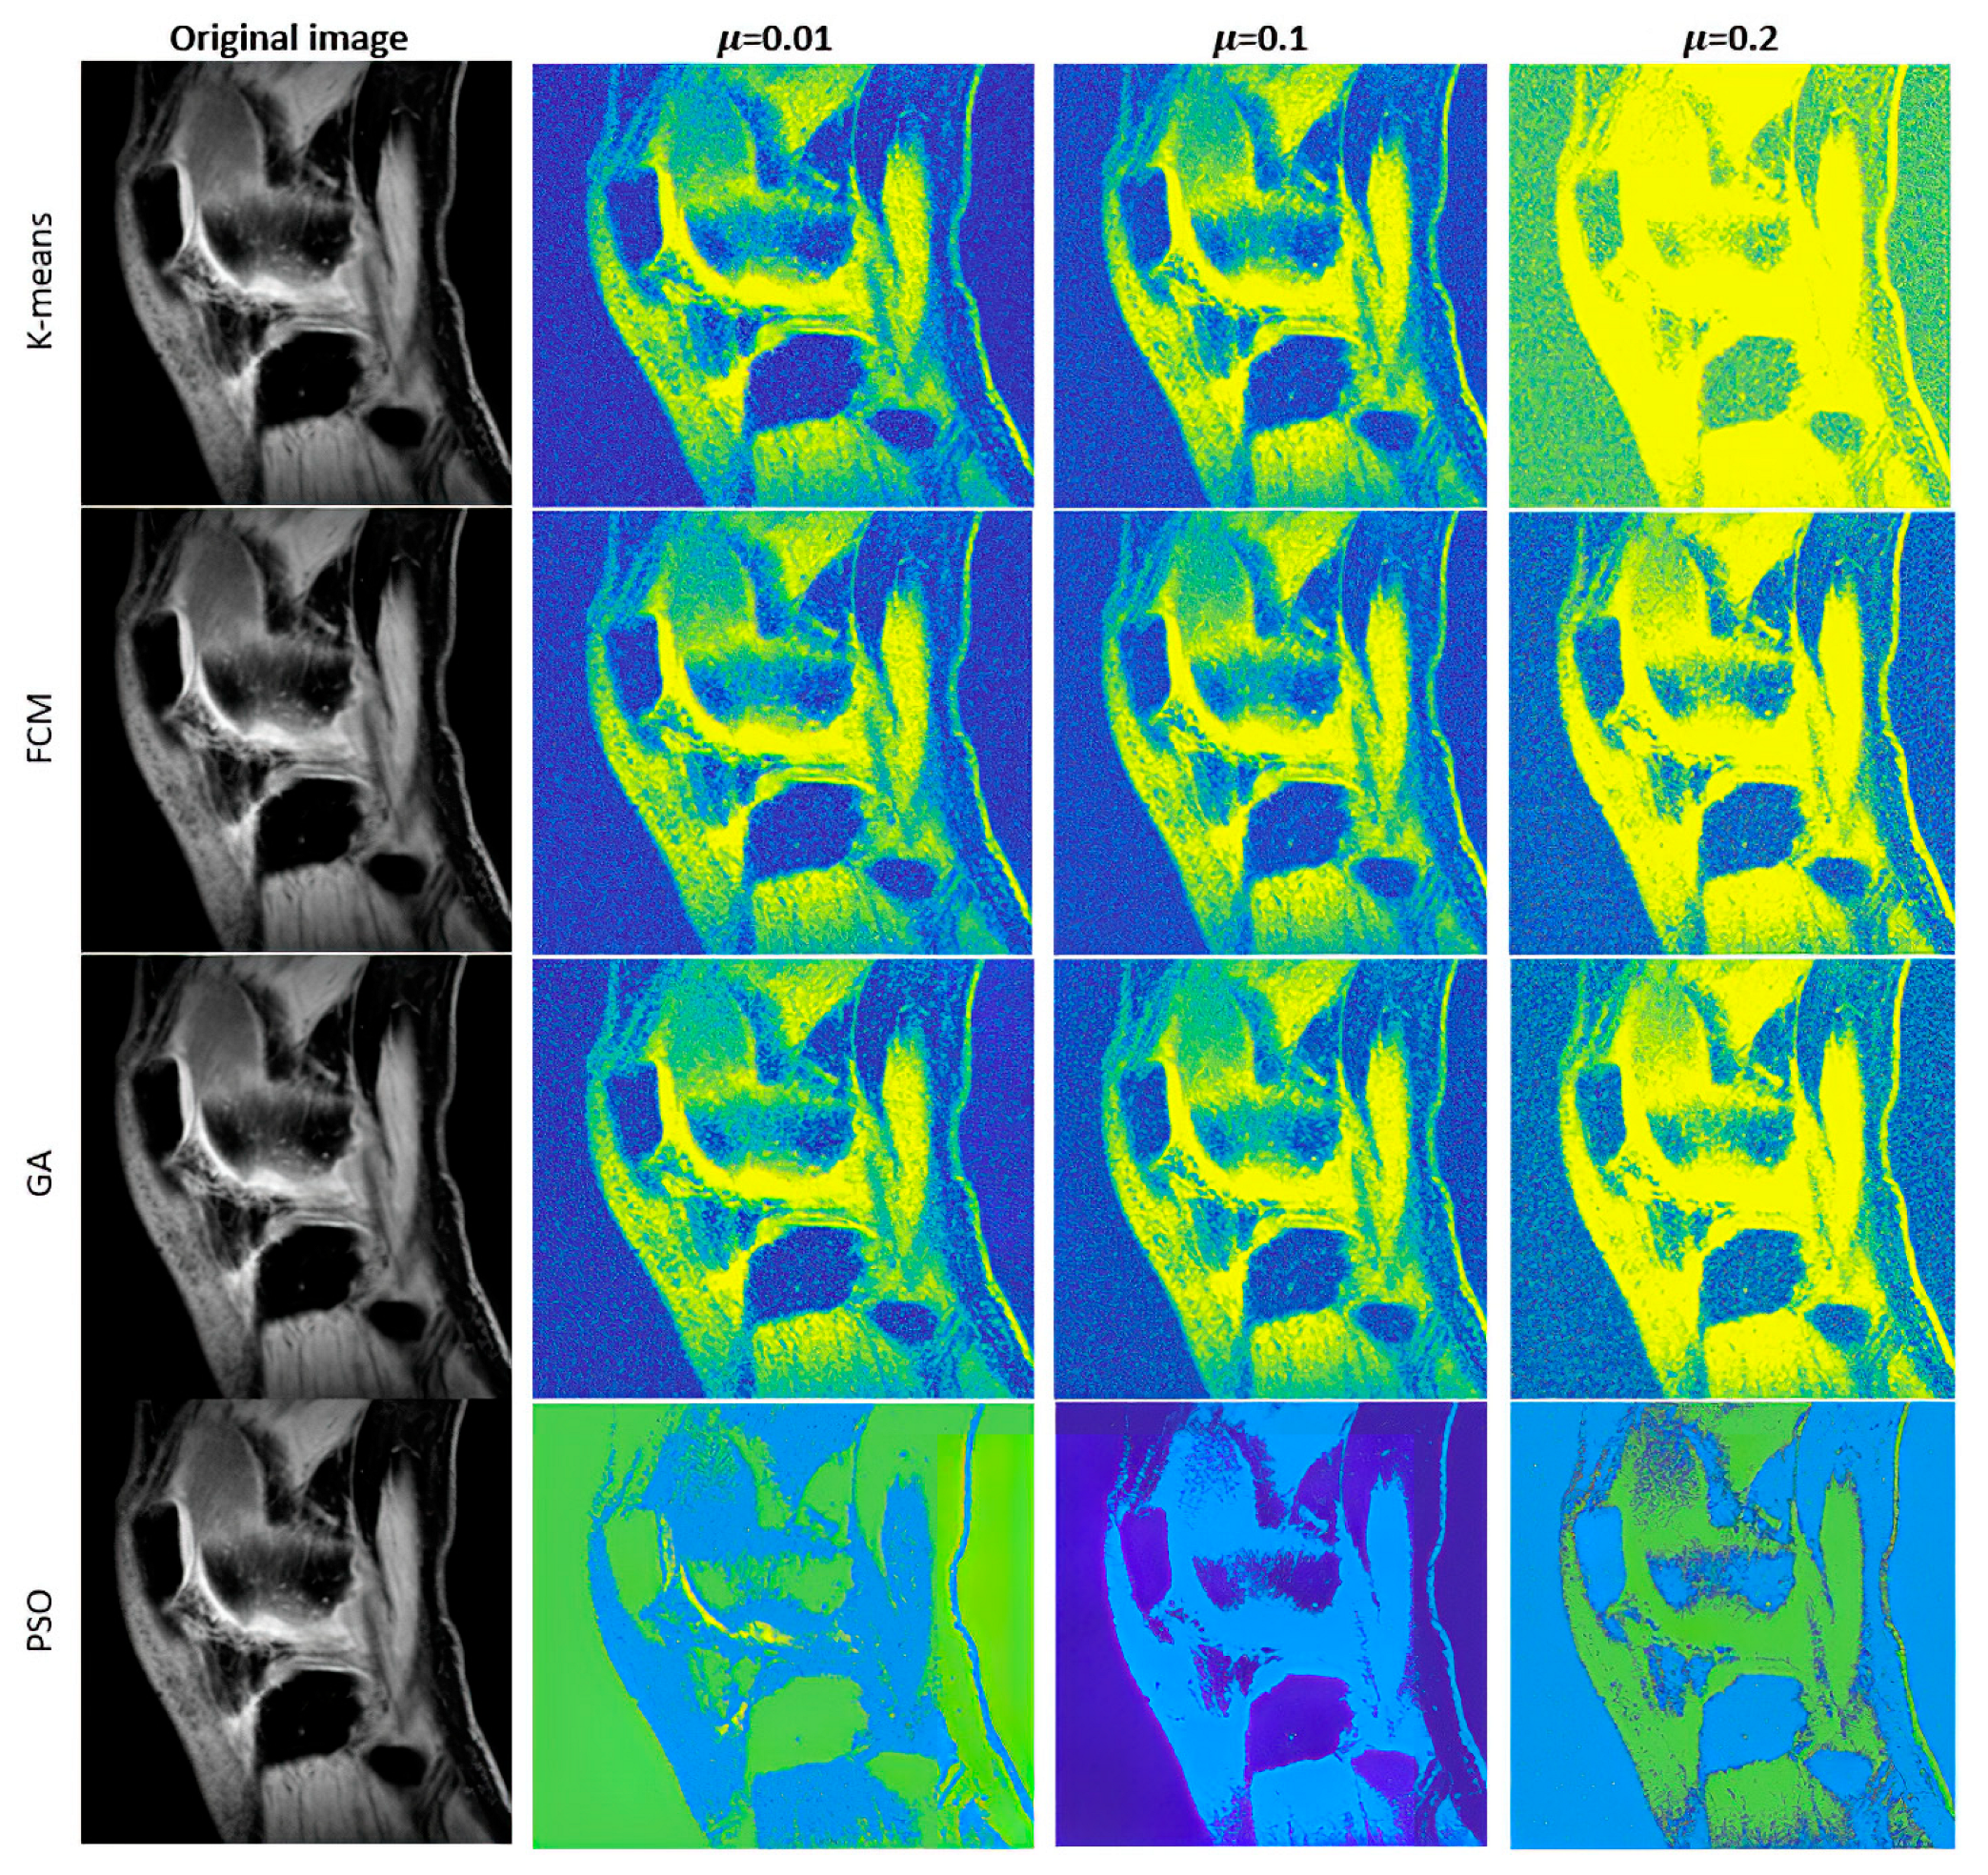

Furthermore, we introduce the graphical comparisons (Figure 4, Figure 5 and Figure 6) of the noise influence on segmentation performance. As we outlined earlier, we designed the analysis, which evaluates the dynamical effect of the noise influence on the segmentation performance. For this purpose, we used three noise generators: Gaussian, Speckle, and Salt and Pepper noise with variable intensity.

Figure 4. Examples of multiregional segmentation maps for optimized clustering schemes with a genetic algorithm (GA) and a PSO with K-means and FCM-based clustering for 4 regions where segmentation is influenced by Gaussian noise with 3 various intensity levels: σ 2 = 0.01 ,   μ = { 0.01 ,   0.1 ,   0.2 } .

Figure 5. Examples of multiregional segmentation maps for optimized clustering schemes with a genetic algorithm (GA) and a PSO with K-means and FCM-based clustering for 4 regions where segmentation is influenced by Speckle noise with 3 various intensity levels: σ 2 = { 0.01 ,   0.1 ,   0.2 } .

Figure 6. Examples of multiregional segmentation maps for optimized clustering schemes with a genetic algorithm (GA) and a PSO with K-means and FCM-based clustering for 4 regions where segmentation is influenced by Salt and Pepper noise with 3 various intensity levels: d = { 0.01 ,   0.1 ,   0.2 } .

Judging by a visual comparison of individual noise generators, the higher the applied noise intensity, the higher the influence on segmentation performance. Nevertheless, just based on the visual comparison, the differences among individual noise types are notable. Significant differences are notable between Speckle and Gaussian noise on the one side and Salt and Pepper noise on the other side, where noise has a higher impact on the segmentation performance. This is caused by the impulse character of the noise, which worsens segmentation performance.